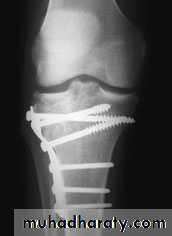

For displaced fractures

treatment is by open reduction and internal fixation with

plate and screws as it is an intra articular fracture.

fixation of tibial plateau fracture